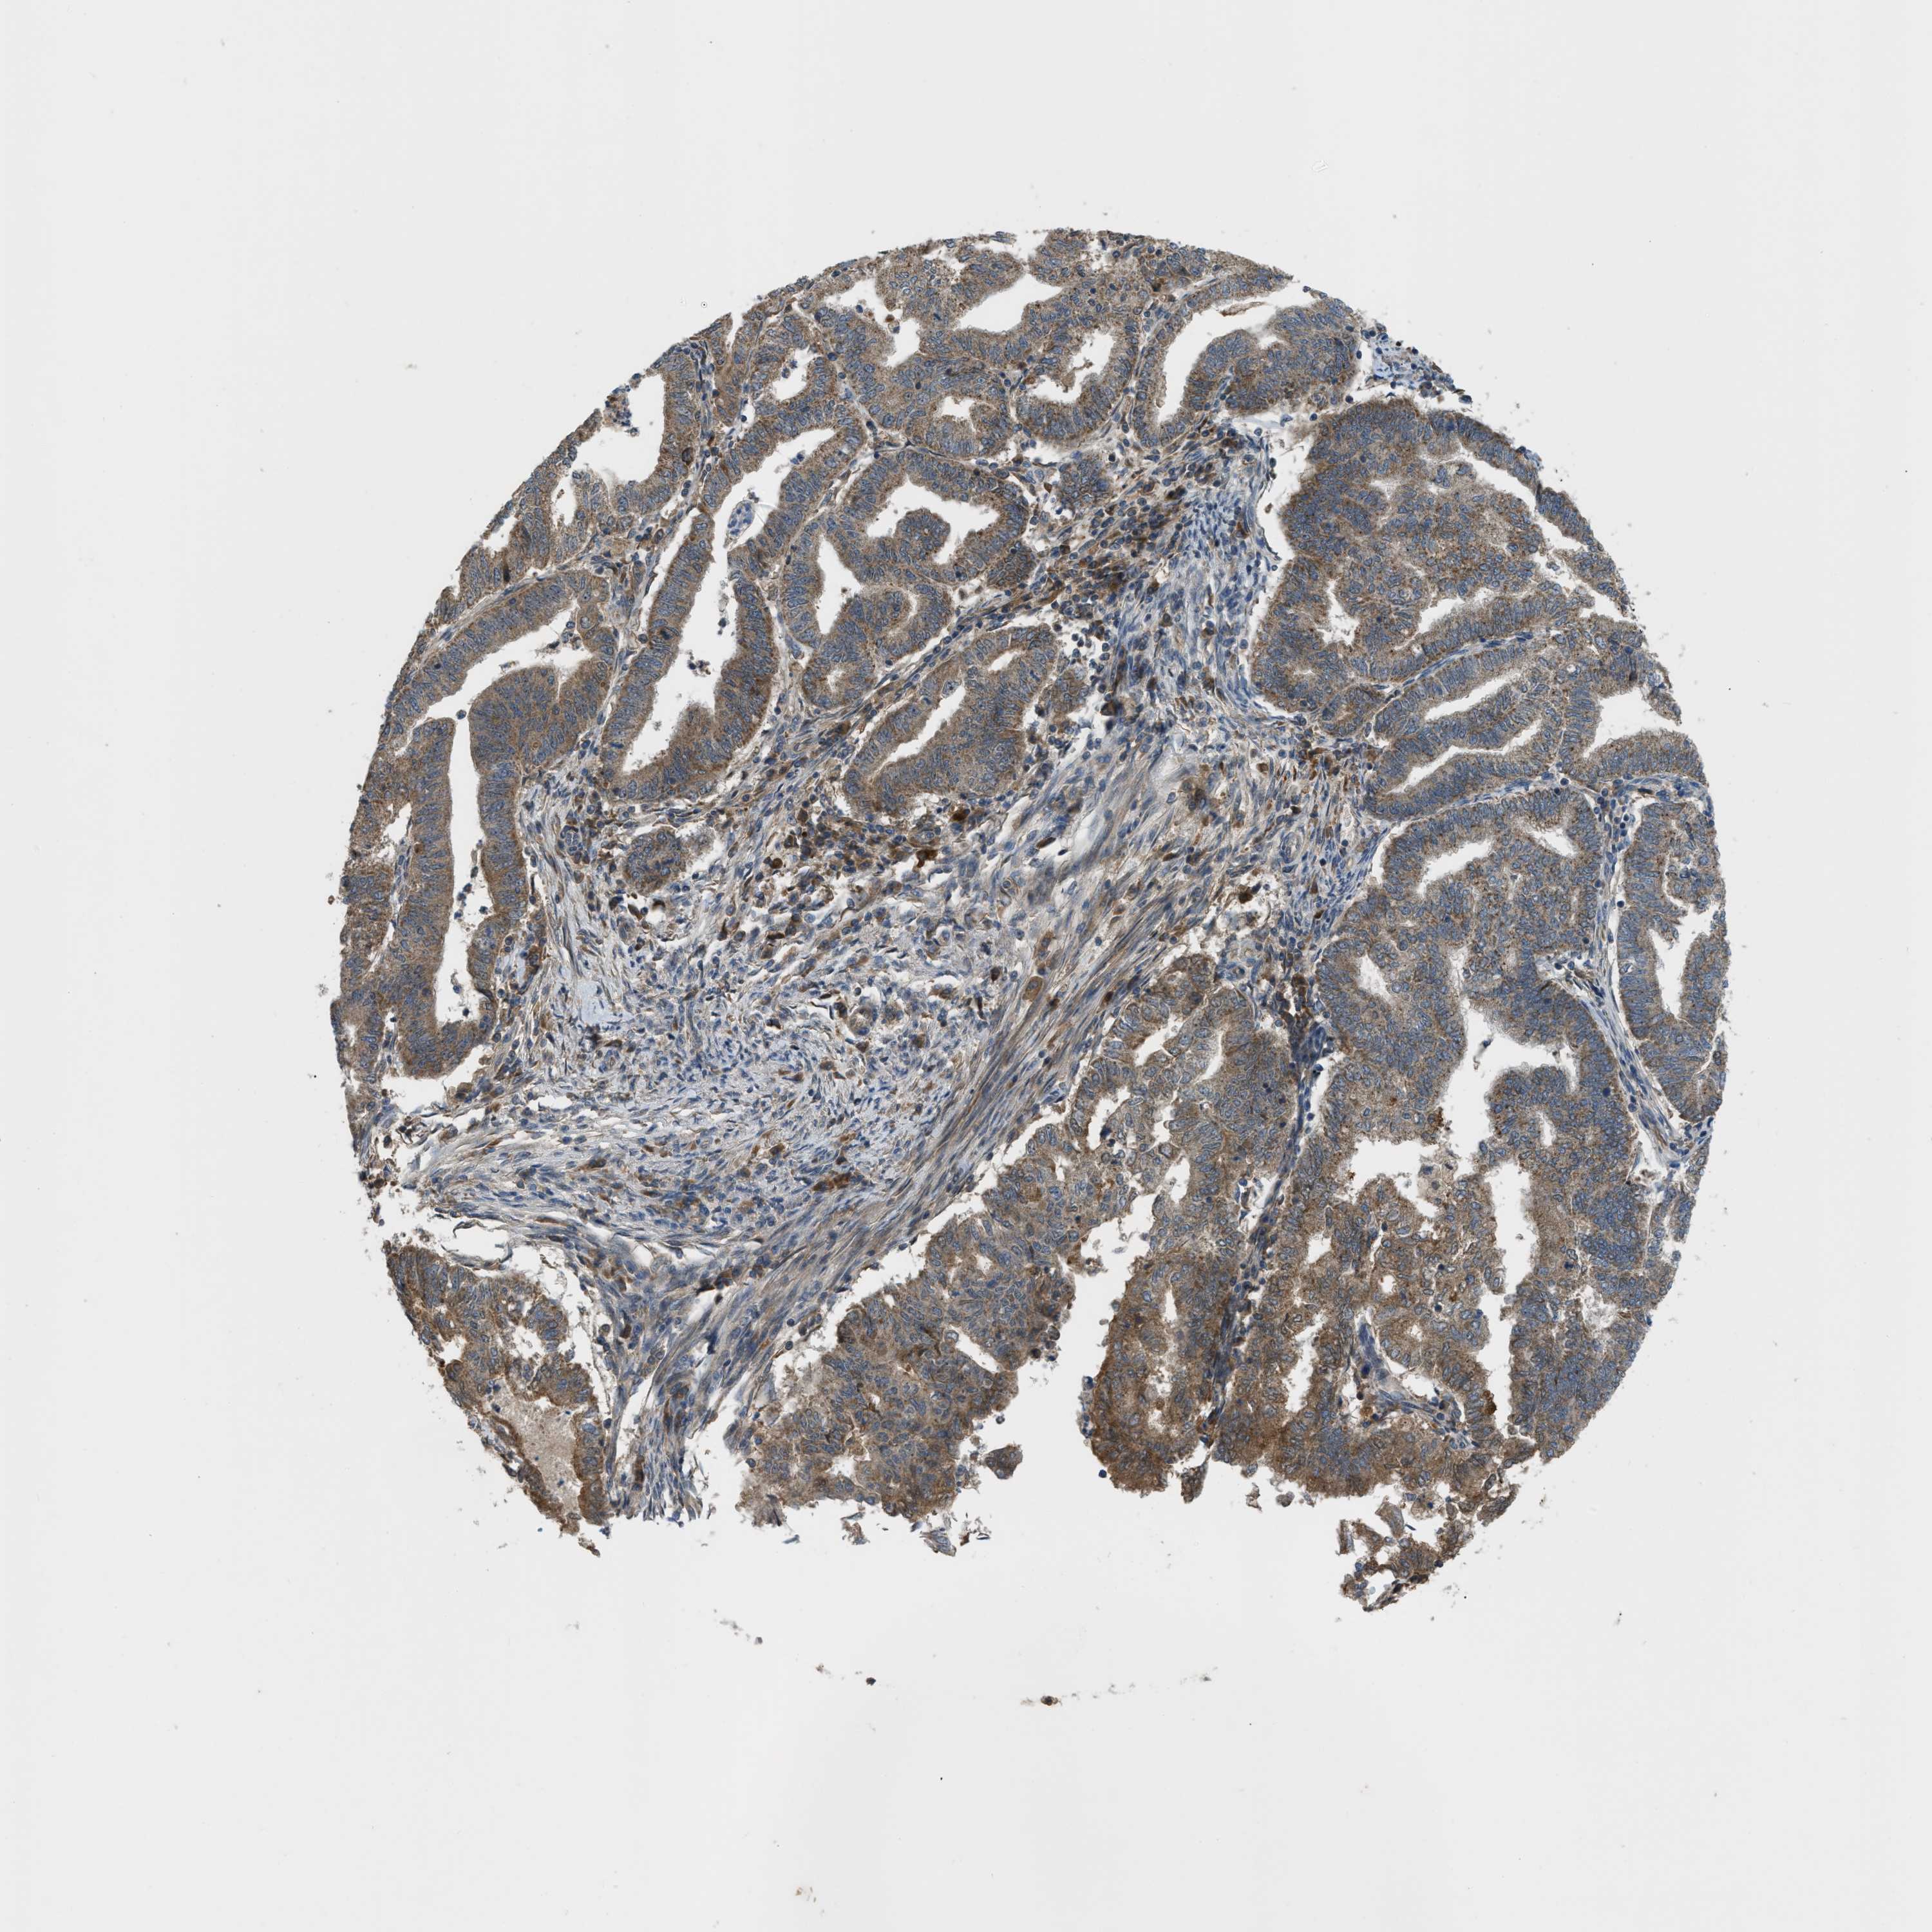

ENDOMETRIAL CANCER - Protein expressioni

A mouse-over function shows sample information and annotation data. Click on an image to view it in a full screen mode. Samples can be filtered based on level of antibody staining by selecting one or several of the following categories: high, medium, low and not detected. The assay and annotation is described here.

Note that samples used for immunohistochemistry by the Human Protein Atlas do not correspond to samples in the TCGA dataset.

Antibody stainingi

Antibody staining in the annotated cell types in the current human tissue is reported as not detected, low, medium, or high, based on conventional immunohistochemistry profiling in selected tissues. This score is based on the combination of the staining intensity and fraction of stained cells.

Each image is clickable and will lead to virtual microscopy that enables deeper exploration of all samples and also displays staining intensity scores, fraction scores and subcellular localization as well as patient and tissue information for each sample.

Antibody HPA018124

Staining

High

Medium

Low

Not detected

Intensity

Strong

Moderate

Weak

Negative

Quantity

>75%

75%-25%

<25%

None

Location

Nuclear

Cytoplasmic/membranous

Cytoplasmic/membranous,nuclear

Adenocarcinoma, NOS

Adenoma, NOS